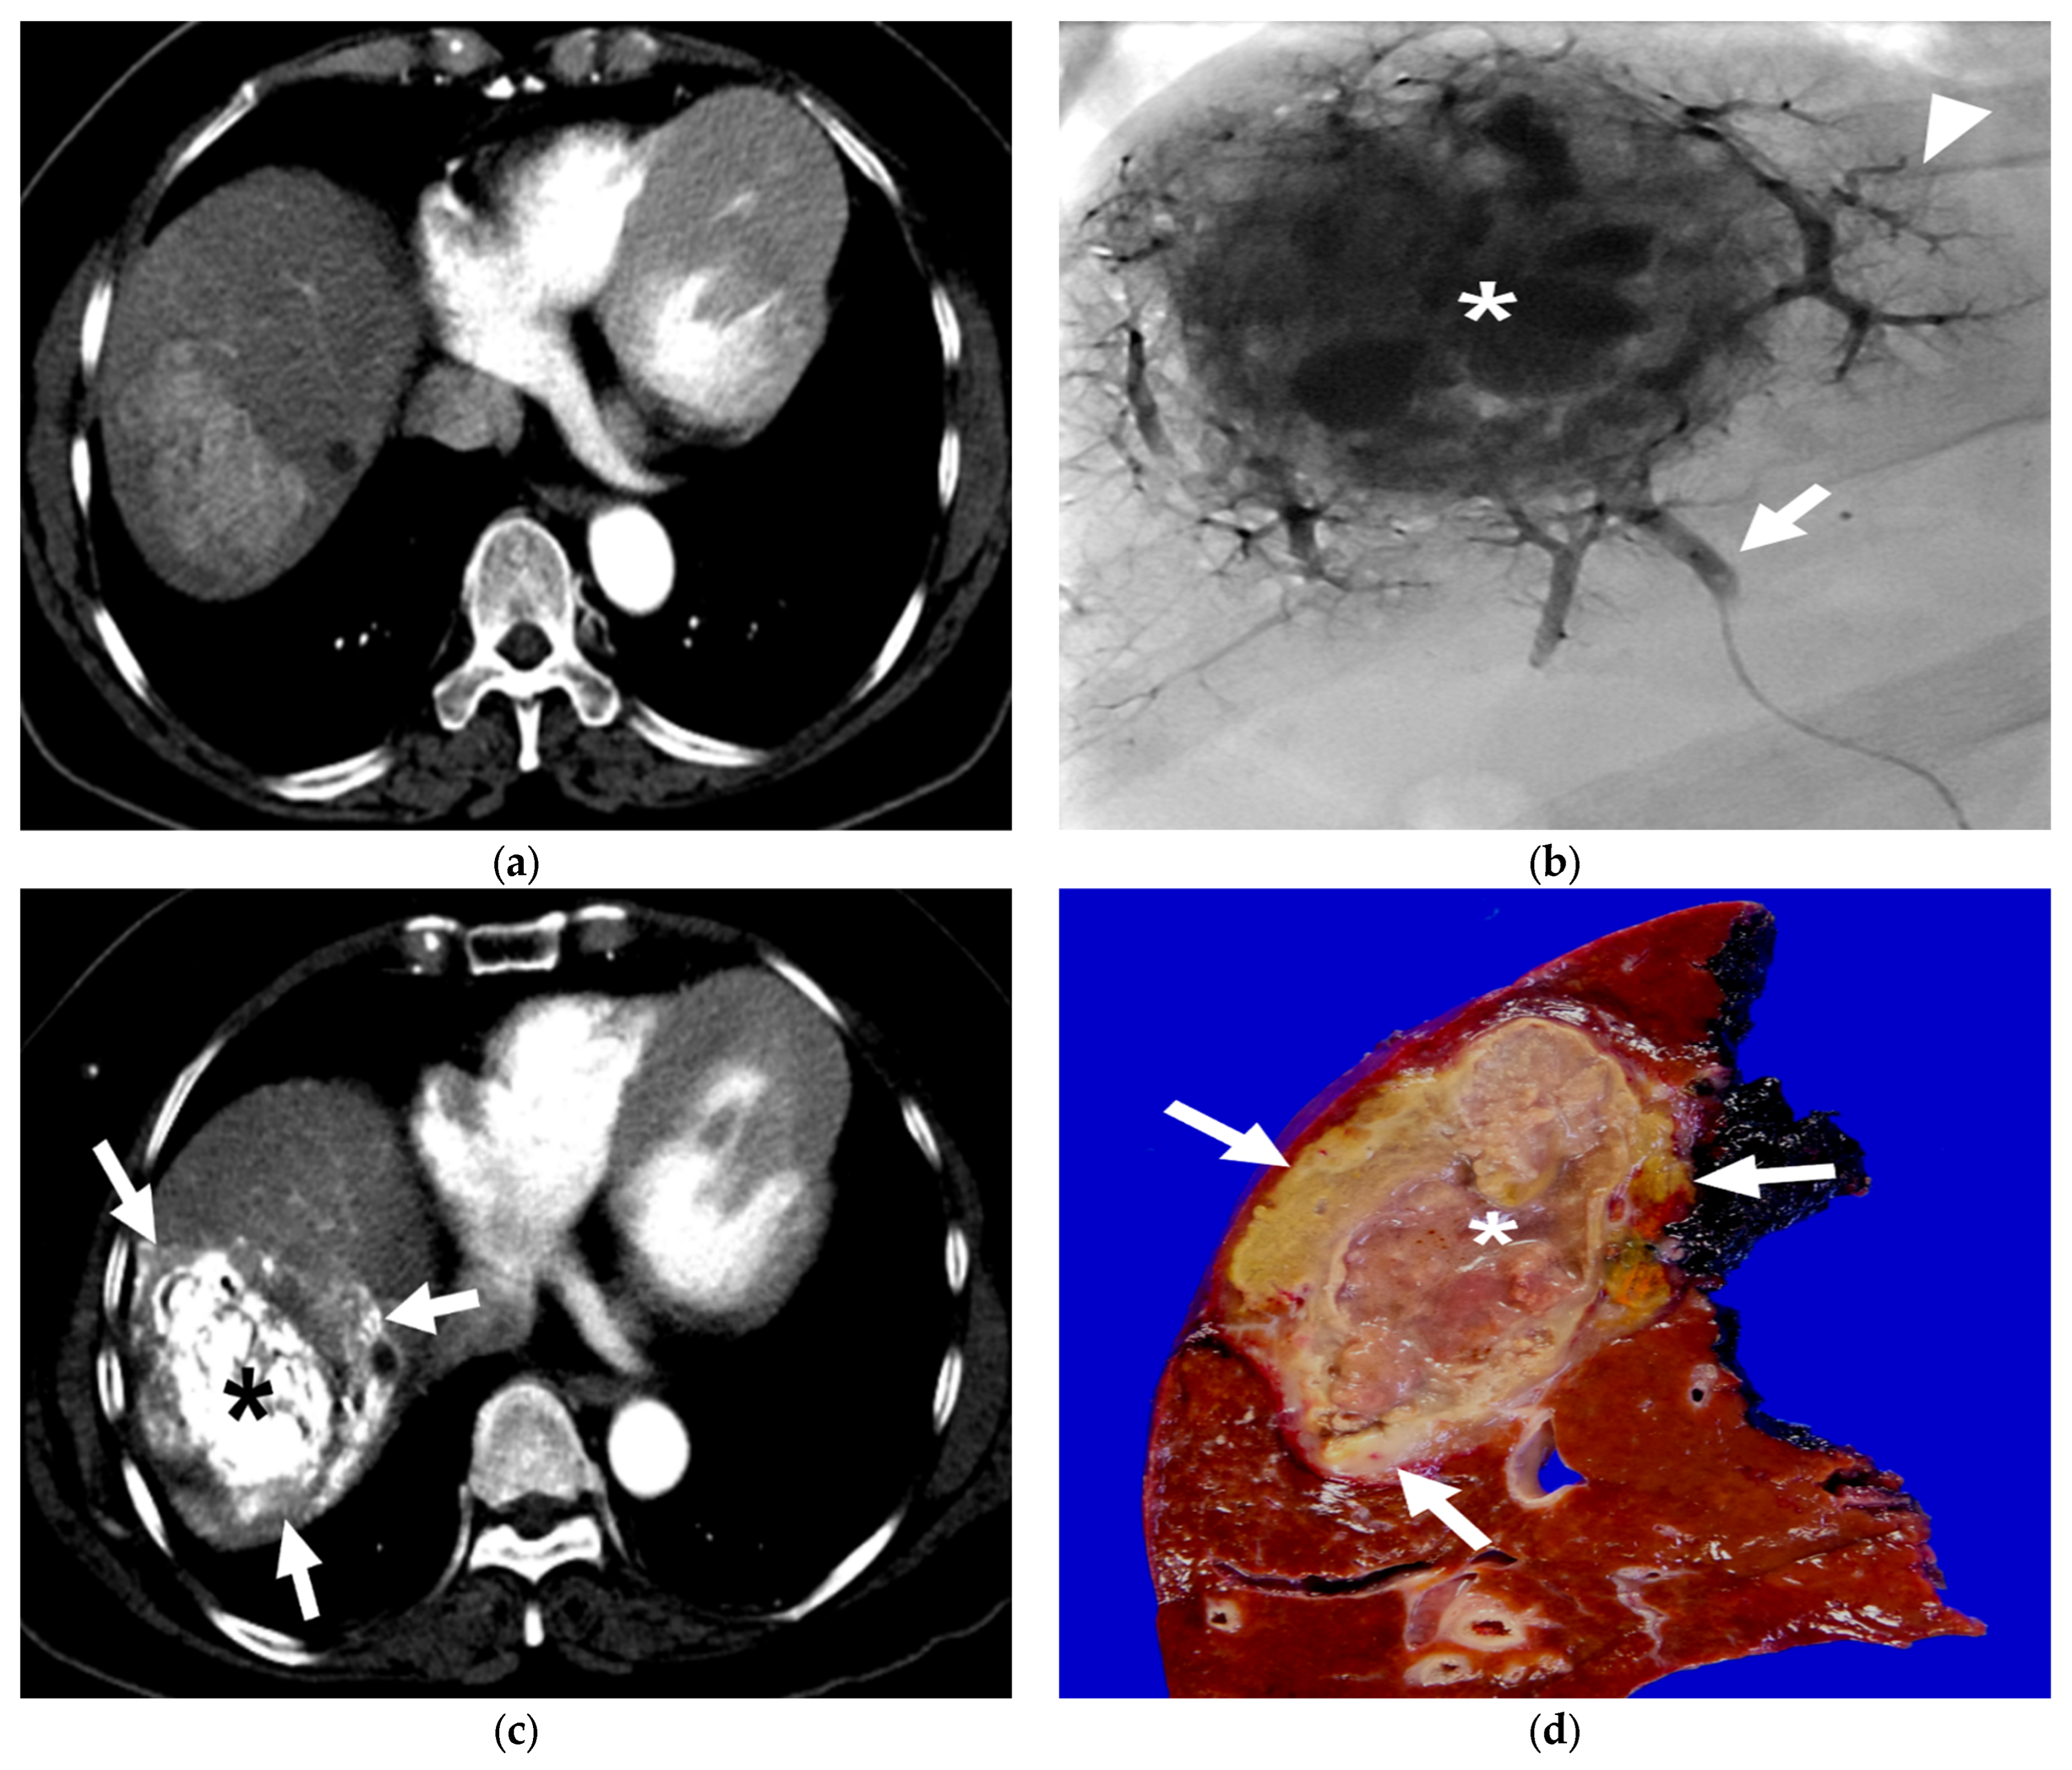

3.2. Radiological and Pathological Outcomes